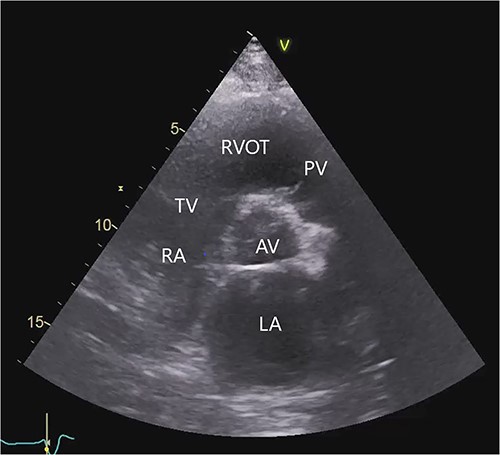

The transthoracic echocardiogram revealed severe dilatation of the left ventricle with a left ventricular end-diastolic diameter of 7.4 cm and a left ventricular systolic function of 15–20% (using Simpson’s biplane method of disks). The size of the right ventricle was normal. The right ventricular systolic function was mildly reduced by visual estimation. There was moderate to severe mitral regurgitation. The aortic valve was normal. The pulmonary and tricuspid valves showed trivial regurgitation (Fig. 1, Video S1 in the Supplementary Material online).

Transthoracic echocardiogram before LVAD implantation. Parasternal short-axis view. AV (aortic valve), LA (left atrium), PV (pulmonary valve), RA (right atrium), RVOT (right ventricular outflow tract), TV (tricuspid valve).